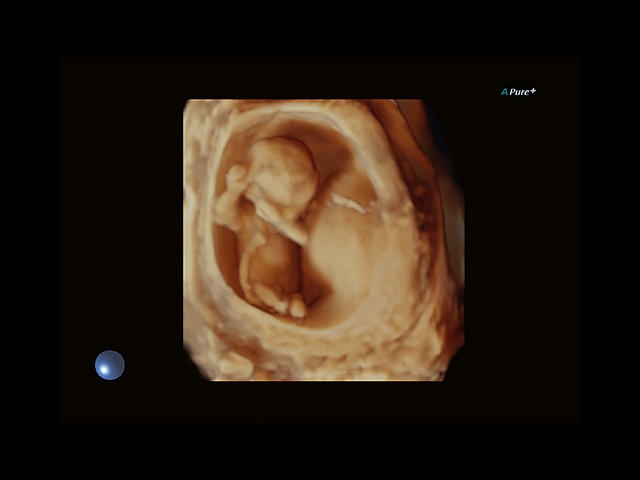

Aplio 500 – ультразвуковой сканер премиум класса, сочетающий в себе быстродействие диагностики и отличное качество визуализации. Более 30 датчиков на выбор, в т.ч. матричные, монокристаллические, 4D, эндоскопические для любых типов исследований. Ультразвуковой сканер позволяет изучать анатомические структуры в высоком разрешении.

Обновленная версия легендарного УЗ-сканера. Стационарный аппарат экспертного класса Aplio 500 Toshiba NEW, визуализирует анатомические структуры в высоком разрешении. Модель позволяет выявить микрокальцификаты, новообразования, нарушения в работе сердца, сосудов и мышц. Присутствует функция виртуальной эндоскопии, 4D-сканирования, эластометрии тканей, УЗИ с контрастированием. За повышение качества изображения отвечают технологии ApliPure и Superb Microvascular Imaging. Первая задействует возможности пространственного и частотного кодирования, формирует цельный визуальный ряд с сохранением клинических маркеров. Вторая улучшает отображение микрососудистого русла, используя доплеровский эффект. Модель оснащена 21-дюймовым монитором, имеет 4 активных порта. Возможно подключение педиатрических, интраоперационных, лапароскопических и чреспищеводных датчиков.